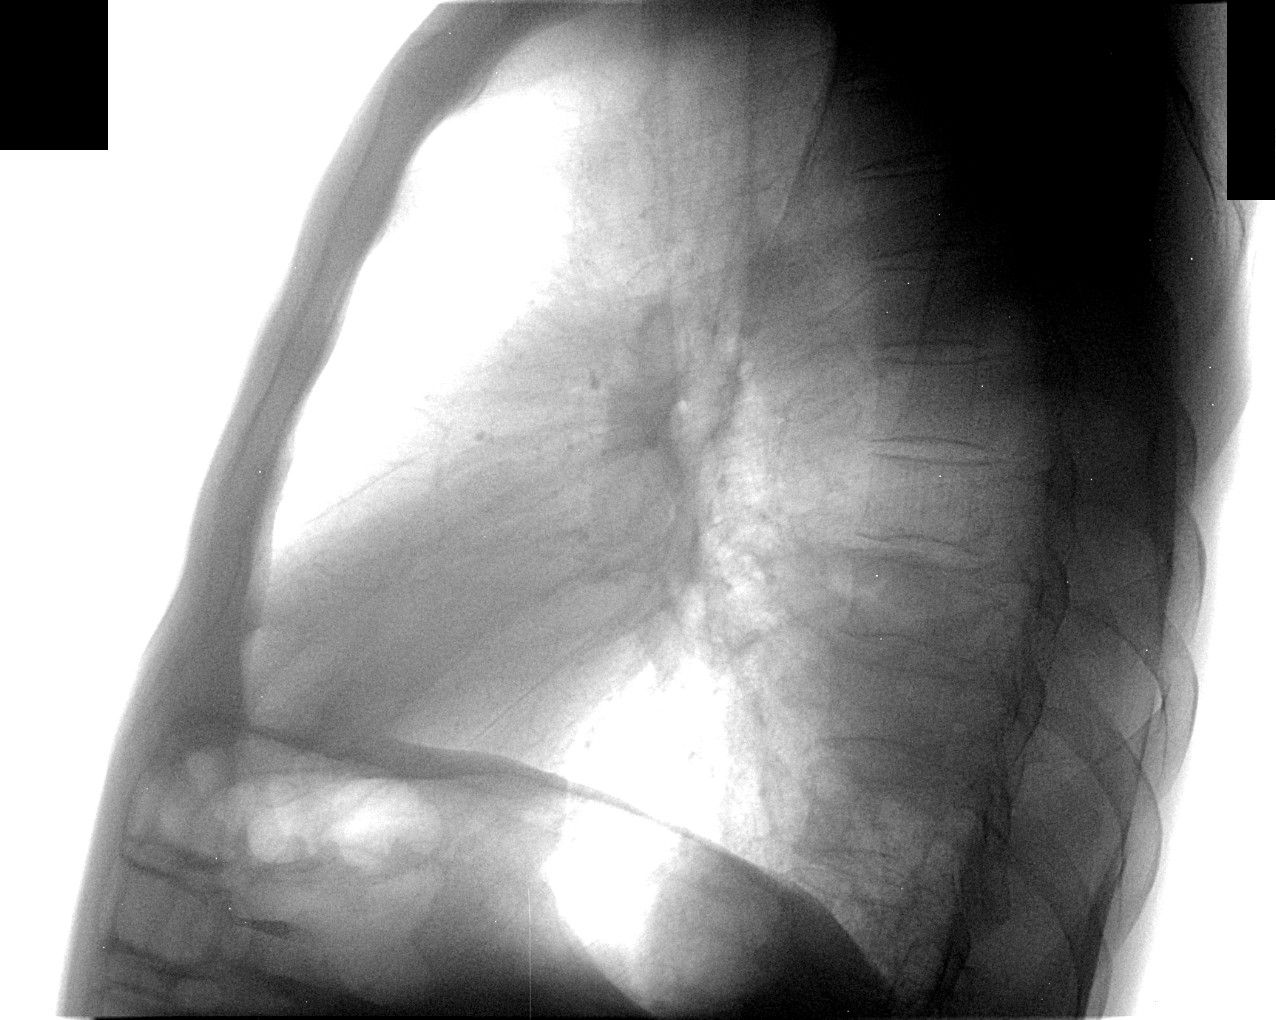

Liev_kosoi.jpg

Через 10 дней направлен повторно, диагноз - пневмония слева. Прямой снимок без признаков инфильтрации, учитывая клинику (интоксикация, гектическая температура, боль в лев. половине гр. кл.), решили посмотреть за сердцем в лев. косом положении, лев. боковой сам Бог велел (снимки представлены). Посмотрели и скопически: в S10 инфильтрация с участками просветления, в заключении написали - пневмония, но термин "абсцедирование" решили не применять, хотя "в уме держали". Больного направили в т/о, там почему-то усомнились в нашей диагностике, пациент вернулся: "меня направляют на Р-гр". Пришлось связаться с терапевтами и прочитать лекцию о том, кто и за что отвечает. На следующий день терапевты с завидным упрямством настаивают на контрольной Р-гр., говорят - боимся абсцедирования, хорошо - говорю, договариваюсь с кэтэшниками, "прокатили" грудную клетку. Но ничего нового, дополнительного не нашли, а "просветлениями" оказались просветы бронхов. Инфильтрация расположена пристеночно, прилежит к позвоночнику с переходом на заднюю стенку гр. клетки, именно в связи с этим никак не прявляет себя на прямом снимке и на боковом выглядит не слишком убедительно. Наиболее оптимальными для такого расположения являются передняя левая или задняя правая косые проекции. Еще через 10 дней, при контрольной рентгеноргафии (прямая и левая боковая), картина без признаков инфильтрации, зная особенности случая, беру за экран и при указанных выше положениях вижу остатки инфильтрации, трактую как "остаточные изменения после пневмонии". Клинически - пациент бъет себя в грудь: "все прекрасно, домой хочу!".

Иконка изображения Liev_kosoi.jpg101.63 КБ